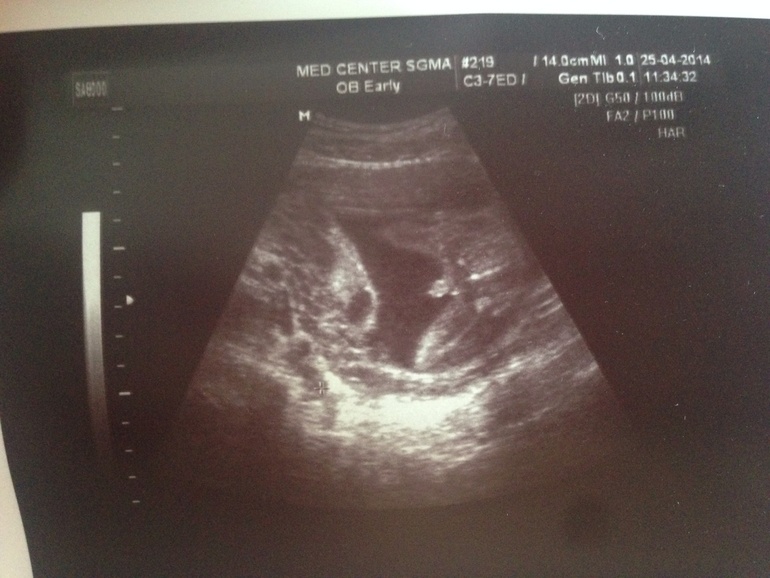

КАК я поняла, на втором фото - это писюн мужской? Поздравляю с хорошим узи.